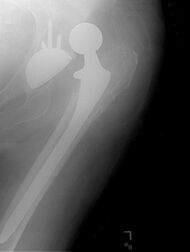

Hemiarthroplasty is a surgical procedure that replaces one half of the joint with an artificial surface and leaves the other part unchanged. This class of procedure is most commonly performed on the hip after an intracapsular fracture of the femur neck (hip fracture). The procedure is performed by removing the head of the femur and replacing it with a metal or composite prosthesis. The most commonly used prosthesis designs are the Austin Moore and Thompson prostheses. A composite of metal and HDPE that forms two interphases (bipolar prosthesis) can be used. The monopolar prosthesis has not been shown to offer any advantage over bipolar designs. The procedure is recommended only for elderly/frail patients, due to their lower life expectancy and activity level. This is because over time the prosthesis tends to loosen or to erode the acetabulum.[84] Independently mobile older adults with hip fractures may benefit from a total hip replacement instead of hemiarthroplasty.[85]

Hip prosthesis for hemiarthroplasty. This example is bipolar, meaning that the head has two separate articulations.